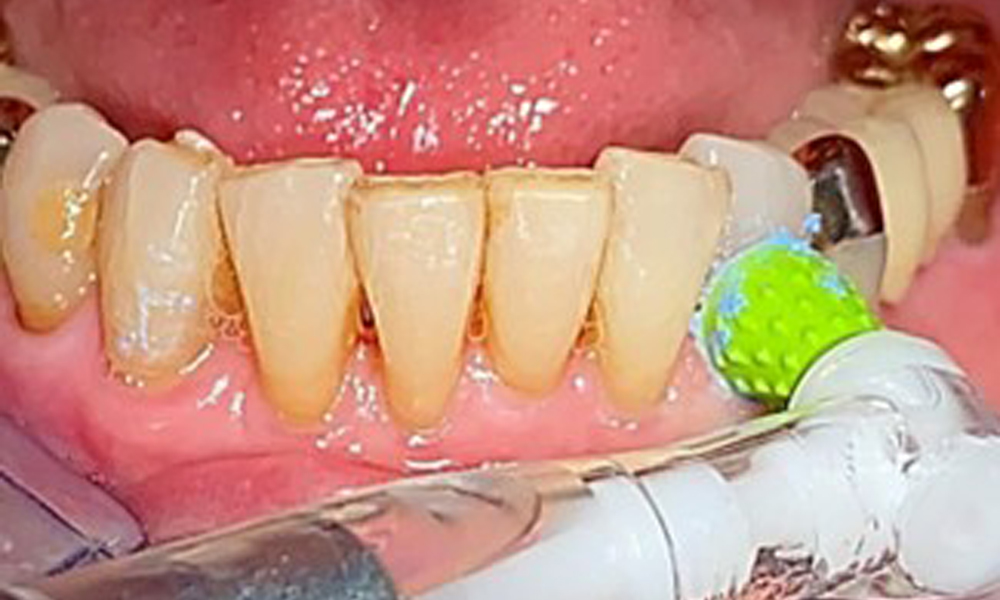

An air polishing system should be used with low-abrasive powder to remove biofilm from the restoration margins, interdental areas and implant surfaces (Fig. 12). Selective polishing (Fig. 13) should be used to smooth any less sensitive areas, as this decreases bacterial reattachment (9).

The dental findings are as follows: Combined removable implant and tooth-supported telescopic prostheses on implants 15, 13, 21, 23, 24, 25 and tooth 11 (Fig. 1, Fig. 2, Fig. 3). The patient was fitted with a fixed mandibular denture. Adequate bridges were present over 37 to 34 and 45 to 47 (Fig. 4), the crown margins were intact and there were no active caries. A composite filling with a marginal gap was present on tooth 43. There was mandibular gingival recession, exposing 1 to 3 mm of root surface. This also applies to 11.

The periodontal condition remains stable. There was no gingival or peri-implant soft tissue inflammation. At 1 to 3 mm, the probing depths were within the physiological range. There are generalised recessions measuring 1 to 3 mm. Implant 23 has an increased probing depth of 4 mm, although there are no signs of secretion or bleeding (Fig. 6). The total BOP is 12%.